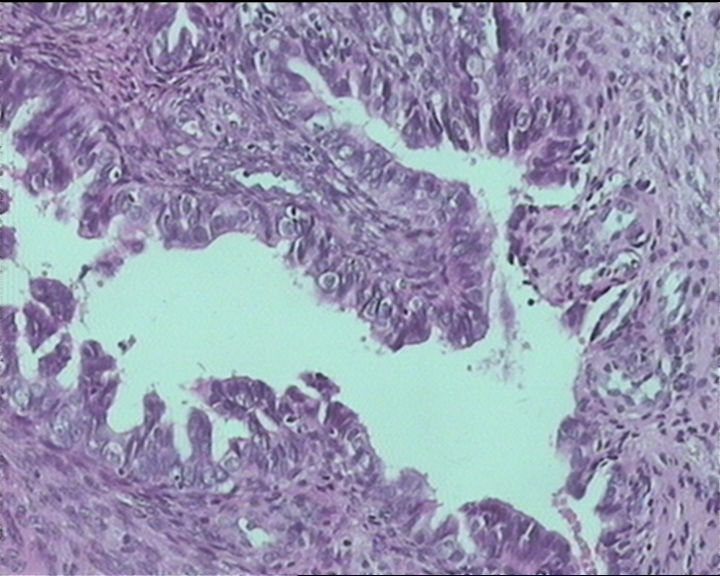

54岁女性,临床“宫颈息肉”送检;巨检:组织一块1。5*1CM,灰红。

输卵管粘膜化生

It is benign. Benign endocervical polyp with tubal metaplasia.

细胞及腺体均有异形,图6、11、16象有纤维间质反应,考虑高级别上皮内瘤变/原位癌,腺癌不能除外。

Sternberg病理学上诊断宫颈原位腺癌的标准是腺体的上皮去粘液分化,呈乳头状或筛网状增生,核分裂易见,这例显然达不到此标准。此例还是归入到腺上皮不典型增生为好。

杨老师说它是良性的,是个颈管内膜息肉伴输卵管上皮化生,良性